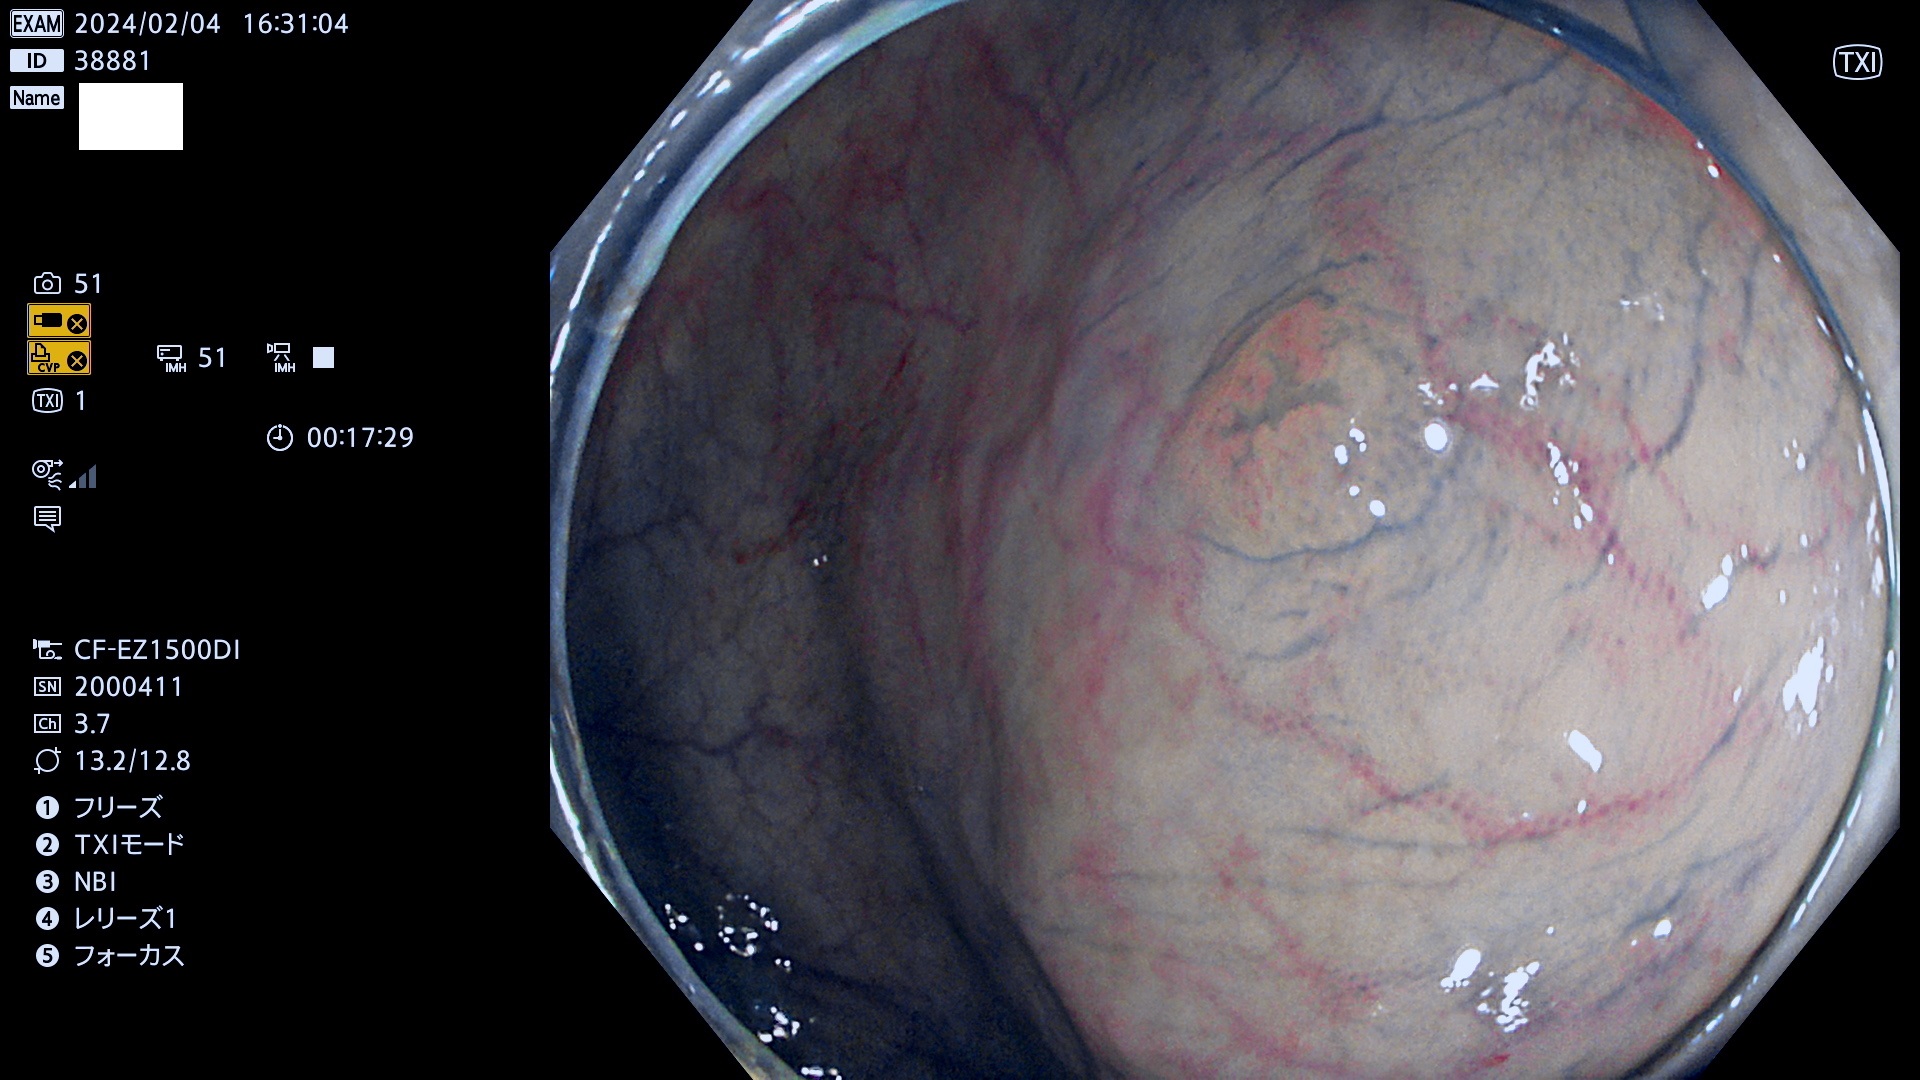

表面型腺腫(Flat Adenoma)の中で、完全に平坦な物をUb、陥凹している物をUcと呼びます。平坦隆起型(Ua)よりも、発見が難しく危険な病変です。

毎週の検査(木・金・土・日)に発見されたUb、Uc型・腺腫を、その週の日曜の夜にUPし1週間、提示します。

抽出の対象期間 2024年2月1日(木)〜2月4(日)の4日間(40件の検査)12件